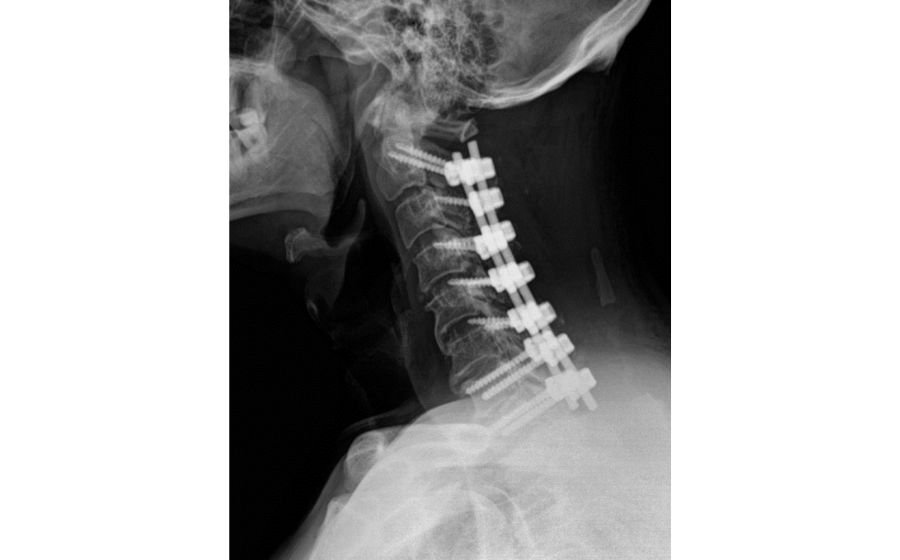

Cervical Lateral Mass Fixation

Cervical lateral mass fixation is a stabilization procedure used to treat neck instability caused by trauma, degeneration, tumors, or previous surgery. Screws and rods are placed into the lateral masses of the cervical vertebrae to restore alignment and protect the spinal cord and nerves. Throughout the procedure, intraoperative neuromonitoring is used to continuously track nerve function, enhancing safety and reducing the risk of neurological injury. This technique provides strong support, improves neck stability, and helps patients return to comfortable and confident movement.